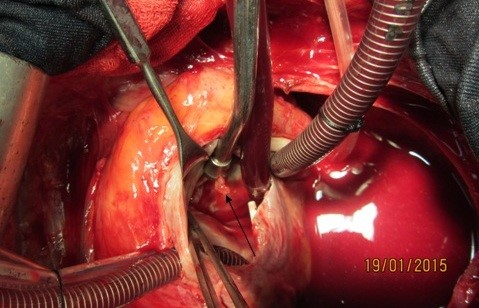

Figure 4: Vegetation on destructive anterior mitral leaflet (black arrow)

Figure 5: Vegetation in entrance of fistula tract to right atrium in tip of suction (black arrow)

A 37-year-old female patient was referred to our hospital following a full course of Brucella endocarditis in a general hospital for emergency surgery of Brucella endocarditis of aortic and mitral valve. The patient’s past medical history revealed living in endemic area of Brucella infection and a history of consumption of unpasteurized milk products. Her medical history was unremarkable except for sacroiliac arthritis. She had been admitted in a general hospital for assessing fever over the last month. After detecting a positive blood culture for Brucella without its bio-typing, she was treated by following triple combination of drugs consisting of oral rifampin 900 mg per day (qd), oral doxycycline 100 mg twice per day (bid) and gentamicin 80 mg intravenously three times per a day (tid) adjusted with blood levels of drugs and serum BUN and creatinine level. Upon admission, the patient was feverous, tachycardic, her blood pressure was low (80/20), and she had dyspnea. On neurologic examination, the patient was awake and oriented; her skin was cold and damp. The patient’s previous blood cultures at three different times showed a Brucella infection. White blood cell count: 12,000/mm–3 with 70% neutrophils, platelet count: 80,000/mm–3, hemoglobin: 9 g/dl, C-reactive protein: 60 mg/dl, erythrocyte sedimentation rate: 75 mm/h, blood urea nitrogen (BUN): 60 mg/dL, and creatine (Cr): 3.9 mg/dL. Urinalysis revealed no hematuria and 24-hour (diurnal) urinalysis (UA) revealed proteinuria. Serum agglutination tests were positive (titer>1:1,500), and enzyme-linked immunosorbent assay tests for anti-Brucella IgG and IgM antibodies were strongly positive (150 U/ml and 52 U/mL, respectively). A transthoracic echocardiogram (TTE) delineated destruction of mitral and aortic valves by multiple vegetation and multiple small and large aortic ring abscesses extended to surrounding tissue and perforated to right atrium, main pulmonary artery and formation a pocket over the left atrial roof (Figure 1 [Fig. 1], Figure 2 [Fig. 2]). The ejection fraction (EF) was 50% and pulmonary pressure was 60 mmHg. There was severe aortic, mitral and tricuspid valve regurgitation. The patient continued to use the previous anti-Brucella drugs orally while additional evaluations were performed. Due to the patient’s congestive heart failure (CHF) in addition to her multiple mobile aortic and mitral valve vegetation, it was decided that aortic and mitral valve replacement shall be performed immediately. The patient was scheduled for an emergency double valves procedure. However, the night before the surgery, she was intubated due to respiratory distress and was subsequently connected to mechanical ventilator. The patient suffered from severe pulmonary edema caused by CHF that required mechanical ventilation. After intubation, the patient became hypotensive and oliguric needing inotropic drugs use. The patient’s hemodynamic became stabilized and she was taken to the operating room. The intra-operative transesophageal echocardiogram (TEE) did not reveal any new findings. The patient was taken to operating room and a median sternotomy was performed and aortic and bi-cava cannulation was done. After opening the pericardium, it was found that the aortic root was severely attached to the surrounding tissue by inflammatory reaction caused by perforation of abscess in left coronary sinus to roof of left atrium as observed in TEE. The ascending aorta was cross-clamped, and after transverse transaction of the ascending aorta, cardioplegin was indirectly infused to coronaries ostium to induce cardiac arrest. After moderate hypothermic cardioplegic arrest, the umbilical tape was put around both the superior vena and inferior vena cavae and they were snared. The right atrium and left atrium were opened superior and inferior to the atrioventricular groove. Further, intra-operative inspection of right atrium showed small vegetations in crater of fistula entrance to right atrium in antero-medial region of tricuspid ring (Figure 3 [Fig. 3]). However, the tricuspid valve was not involved in infective endocarditis. Intra-aortic root inspection revealed a defect in non-aortic coronary sinus filled with necrotic materials and an abscess that perforated through the area above the tricuspid valve (Figure 4 [Fig. 4]). There was also a fistula between the left-coronary sinus, just near the left coronary ostium to the main pulmonary artery (Figure 5 [Fig. 5]). Further intra-operative perception of aortic root revealed a pocket filled by abscess through a defect in left coronary sinus just located over the roof of the left atrium (Figure 6 [Fig. 6]). In addition to the aforementioned fistulas, multiple vegetations were observed on both mitral and aortic valves that caused severe destruction of both valves causing grave regurgitation (Figure 7 [Fig. 7]). It apeared that mitral valve vegetations were caused by regurgitated aortic valve flow that impinged on aorto-mitral fibrous continuity and subsequently caused the penetration and destruction of the native mitral valve (Figure 8 [Fig. 8]). This infective tissue involved the valve. The abscess was completely debrided to restore and find underlying normal tissue. After debridement of the perforation’s site of the left coronary sinus and cleaning of the performed pocket over the left atrial roof, the aortic defect was repaired by fresh autologous pericardium patch that was used in the external side of the ascending aorta. The fistula tract to main pulmonary artery was closed from intra-pulmonary side of fistula by 4/0 proline sutures, as the closure of small fistula to right atrium. After closing of all three fistula and reconstructing the left sinus of valsalva and replacement of both valves, an oval-shaped fresh pericardial patch was utilized in a sino-tubular junction positioned just close to the superior vena cava, which helped in a tension-free approximation of aortotomy incision. Because the perforation of abscess along the conduction system caused bundle branch block and disturbances of other conduction branches, the atrial and ventricular epicardial pacing wires were used for sequential atro-ventricular pacing. The patient was admitted to the surgical intensive care unit for further control and treatment. Weaning from mechanical ventilation was complicated with tachypnea and grave respiratory distress. Extubation was delayed on the 9th post-operative day after performing a tracheostomy for the better cleaning of respiratory tract secretion and facilitation of extubation. Transient renal and hepatic failure also complicated the postoperative course of surgery. The serum blood nitrogen and creatinine raised to 90 and 5.5 subsequently and was managed accordingly by three times of peritoneal dialysis. Her hepatic and kidney dysfunction recovered relatively in 15th day of operation. A TEE in discharge time revealed a normal functioning of both bioprosthetic valves; however, a mild paravalvular leakage was observed in aortic position. Moreover, correction of all fistulas was successful and no residual flow signal in area of fistula repair was found. She was discharged home on the 25th day after admission.